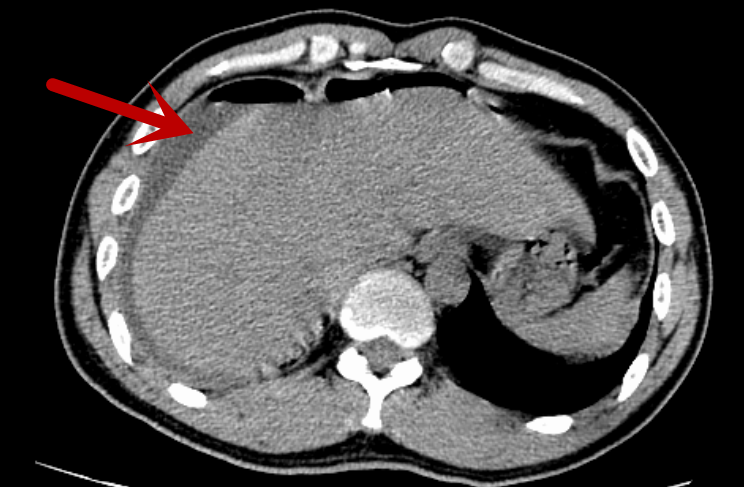

术前CT,箭头所指为腹腔积脓

37岁男性患者唐某,因突发腹痛8小时于2026年1月8日急诊入院,呈刀割样剧烈疼痛,难以忍受。入院查体:急性病容,腹肌紧张,上腹部、右上下腹部压痛、反跳痛明显,肠鸣音减弱,约1次/分。腹膜炎体征明显,入院予急诊完善腹部CT检查提示:1.气腹,考虑消化道穿孔。2.阑尾粪石,并阑尾炎。3.腹腔积液。因病变部位不同,胃穿孔的病变解剖部位在上腹部,阑尾炎的病变解剖部位在右下腹,考虑要兼顾上下腹、充分显露手术部位等,传统手术需在腹壁开10cm-15cm的较长切口,手术创伤大,恢复慢。医生决定采用腹腔镜手术,只在腹壁打3-4个0.5cm-1.0cm戳孔就能完成手术。